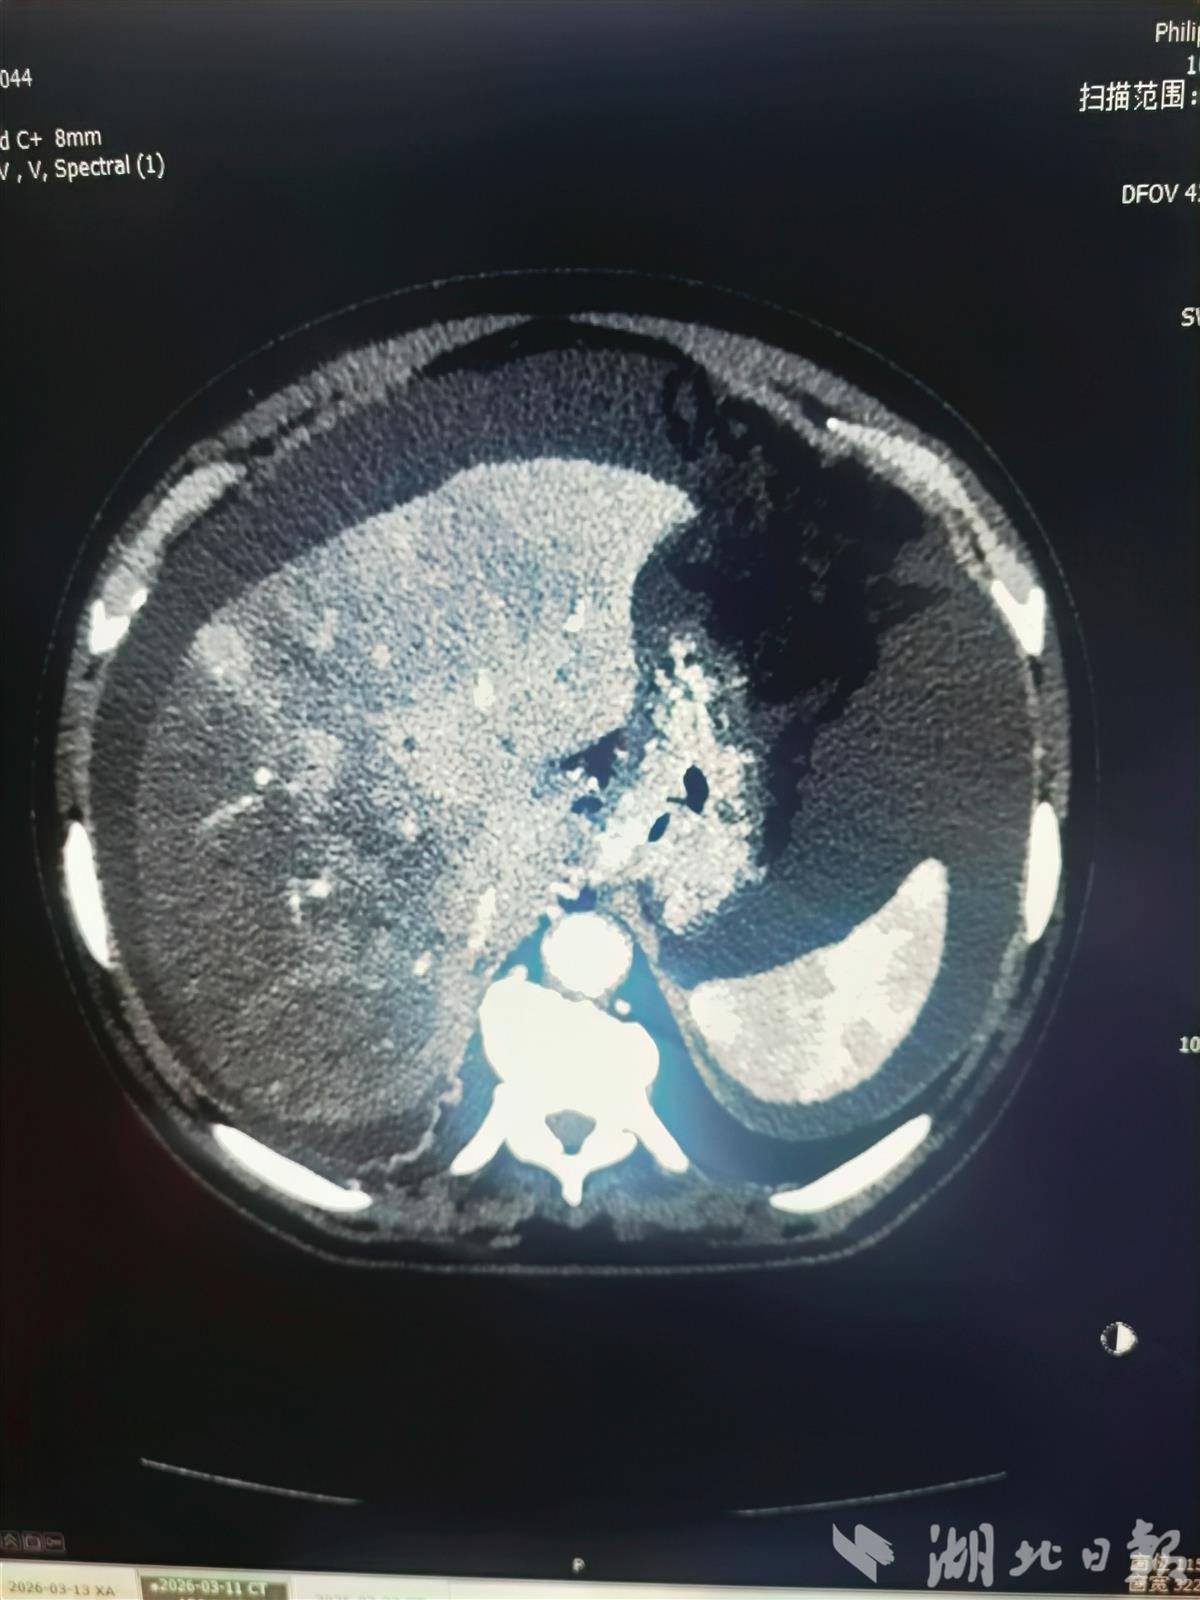

影像检查下可见患者损伤的肝脏和大量腹水。(受访单位供图)

医生检查后发现,杜先生的肝脏已经严重受损,大量腹水积聚在腹腔内,药物已无法控制。经过详细评估,介入科阚雪锋教授团队决定为他实施一种名为“经颈静脉肝内门体分流术(TIPS)”的微创手术。

杜先生平日注重养生,偶然听说“土三七”泡酒对身体有益,便自行制作并饮用。两个月后,他开始出现严重腹胀、腹痛,肚子像吹气球一样鼓了起来,在当地医院被诊断为“肝小静脉闭塞症”。这是一种因肝脏内部小血管堵塞、血液无法正常流出而导致的严重肝病,可引发顽固性腹水、肝功能衰竭,甚至致命。